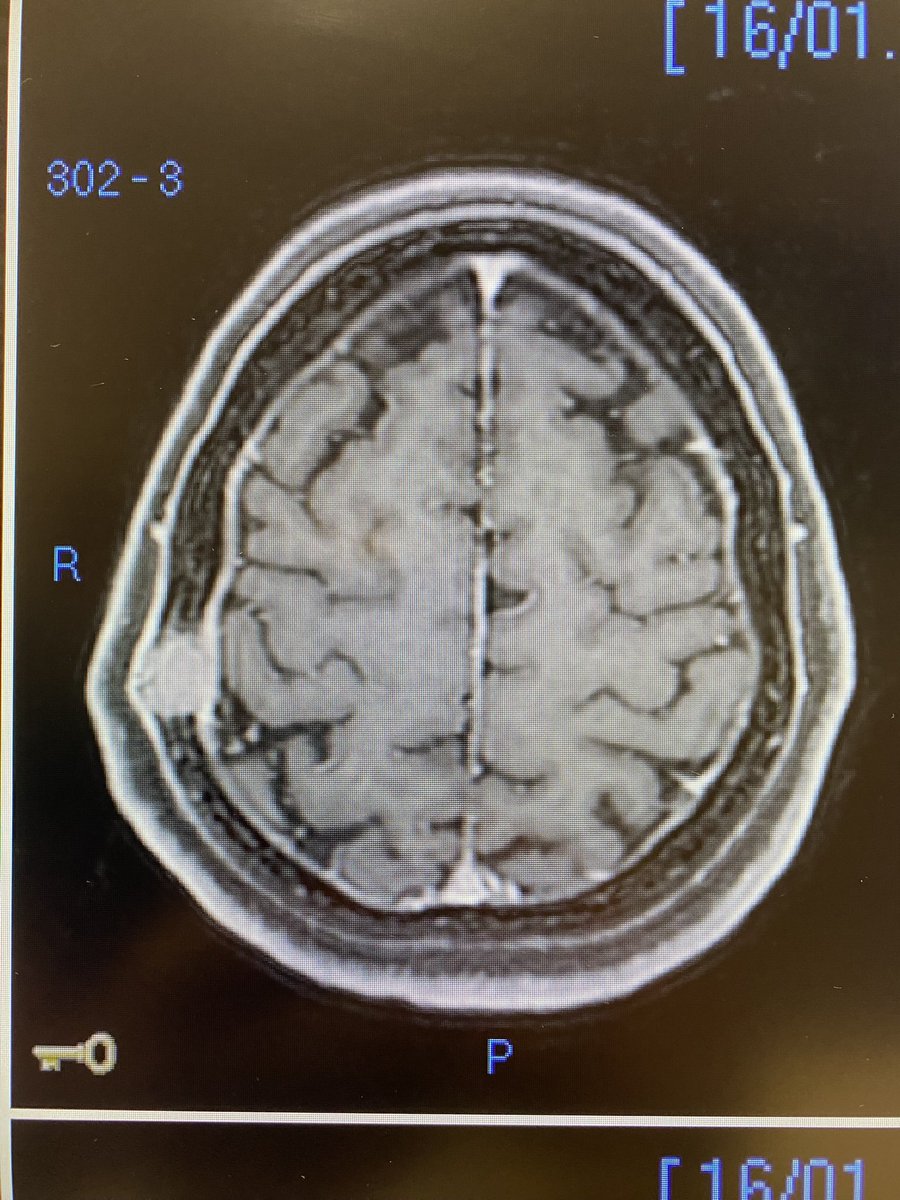

49yo, female, sporadic/acquired FH deficient Papillary Renal Cell Carcinoma with bone-only recurrence 10m after nefrectomy. Only 2 mets, but symptomatic (pain) and growing towards the brain. Radioresistant…